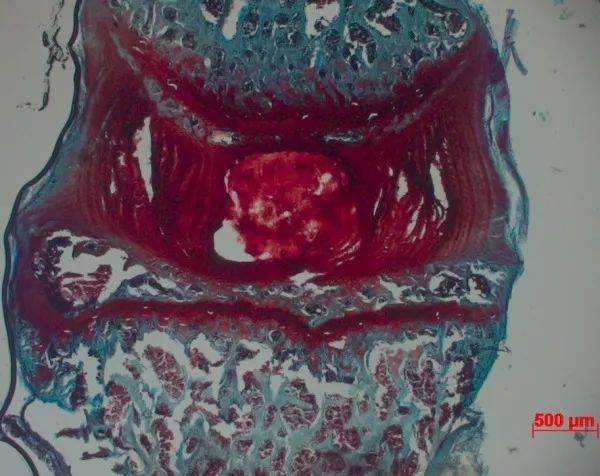

纤维环疤痕愈合图,纤维环慢慢恢复图

纤维环慢慢恢复图

腰椎纤维环疤痕愈合图

纤维环撕裂

纤维环破裂